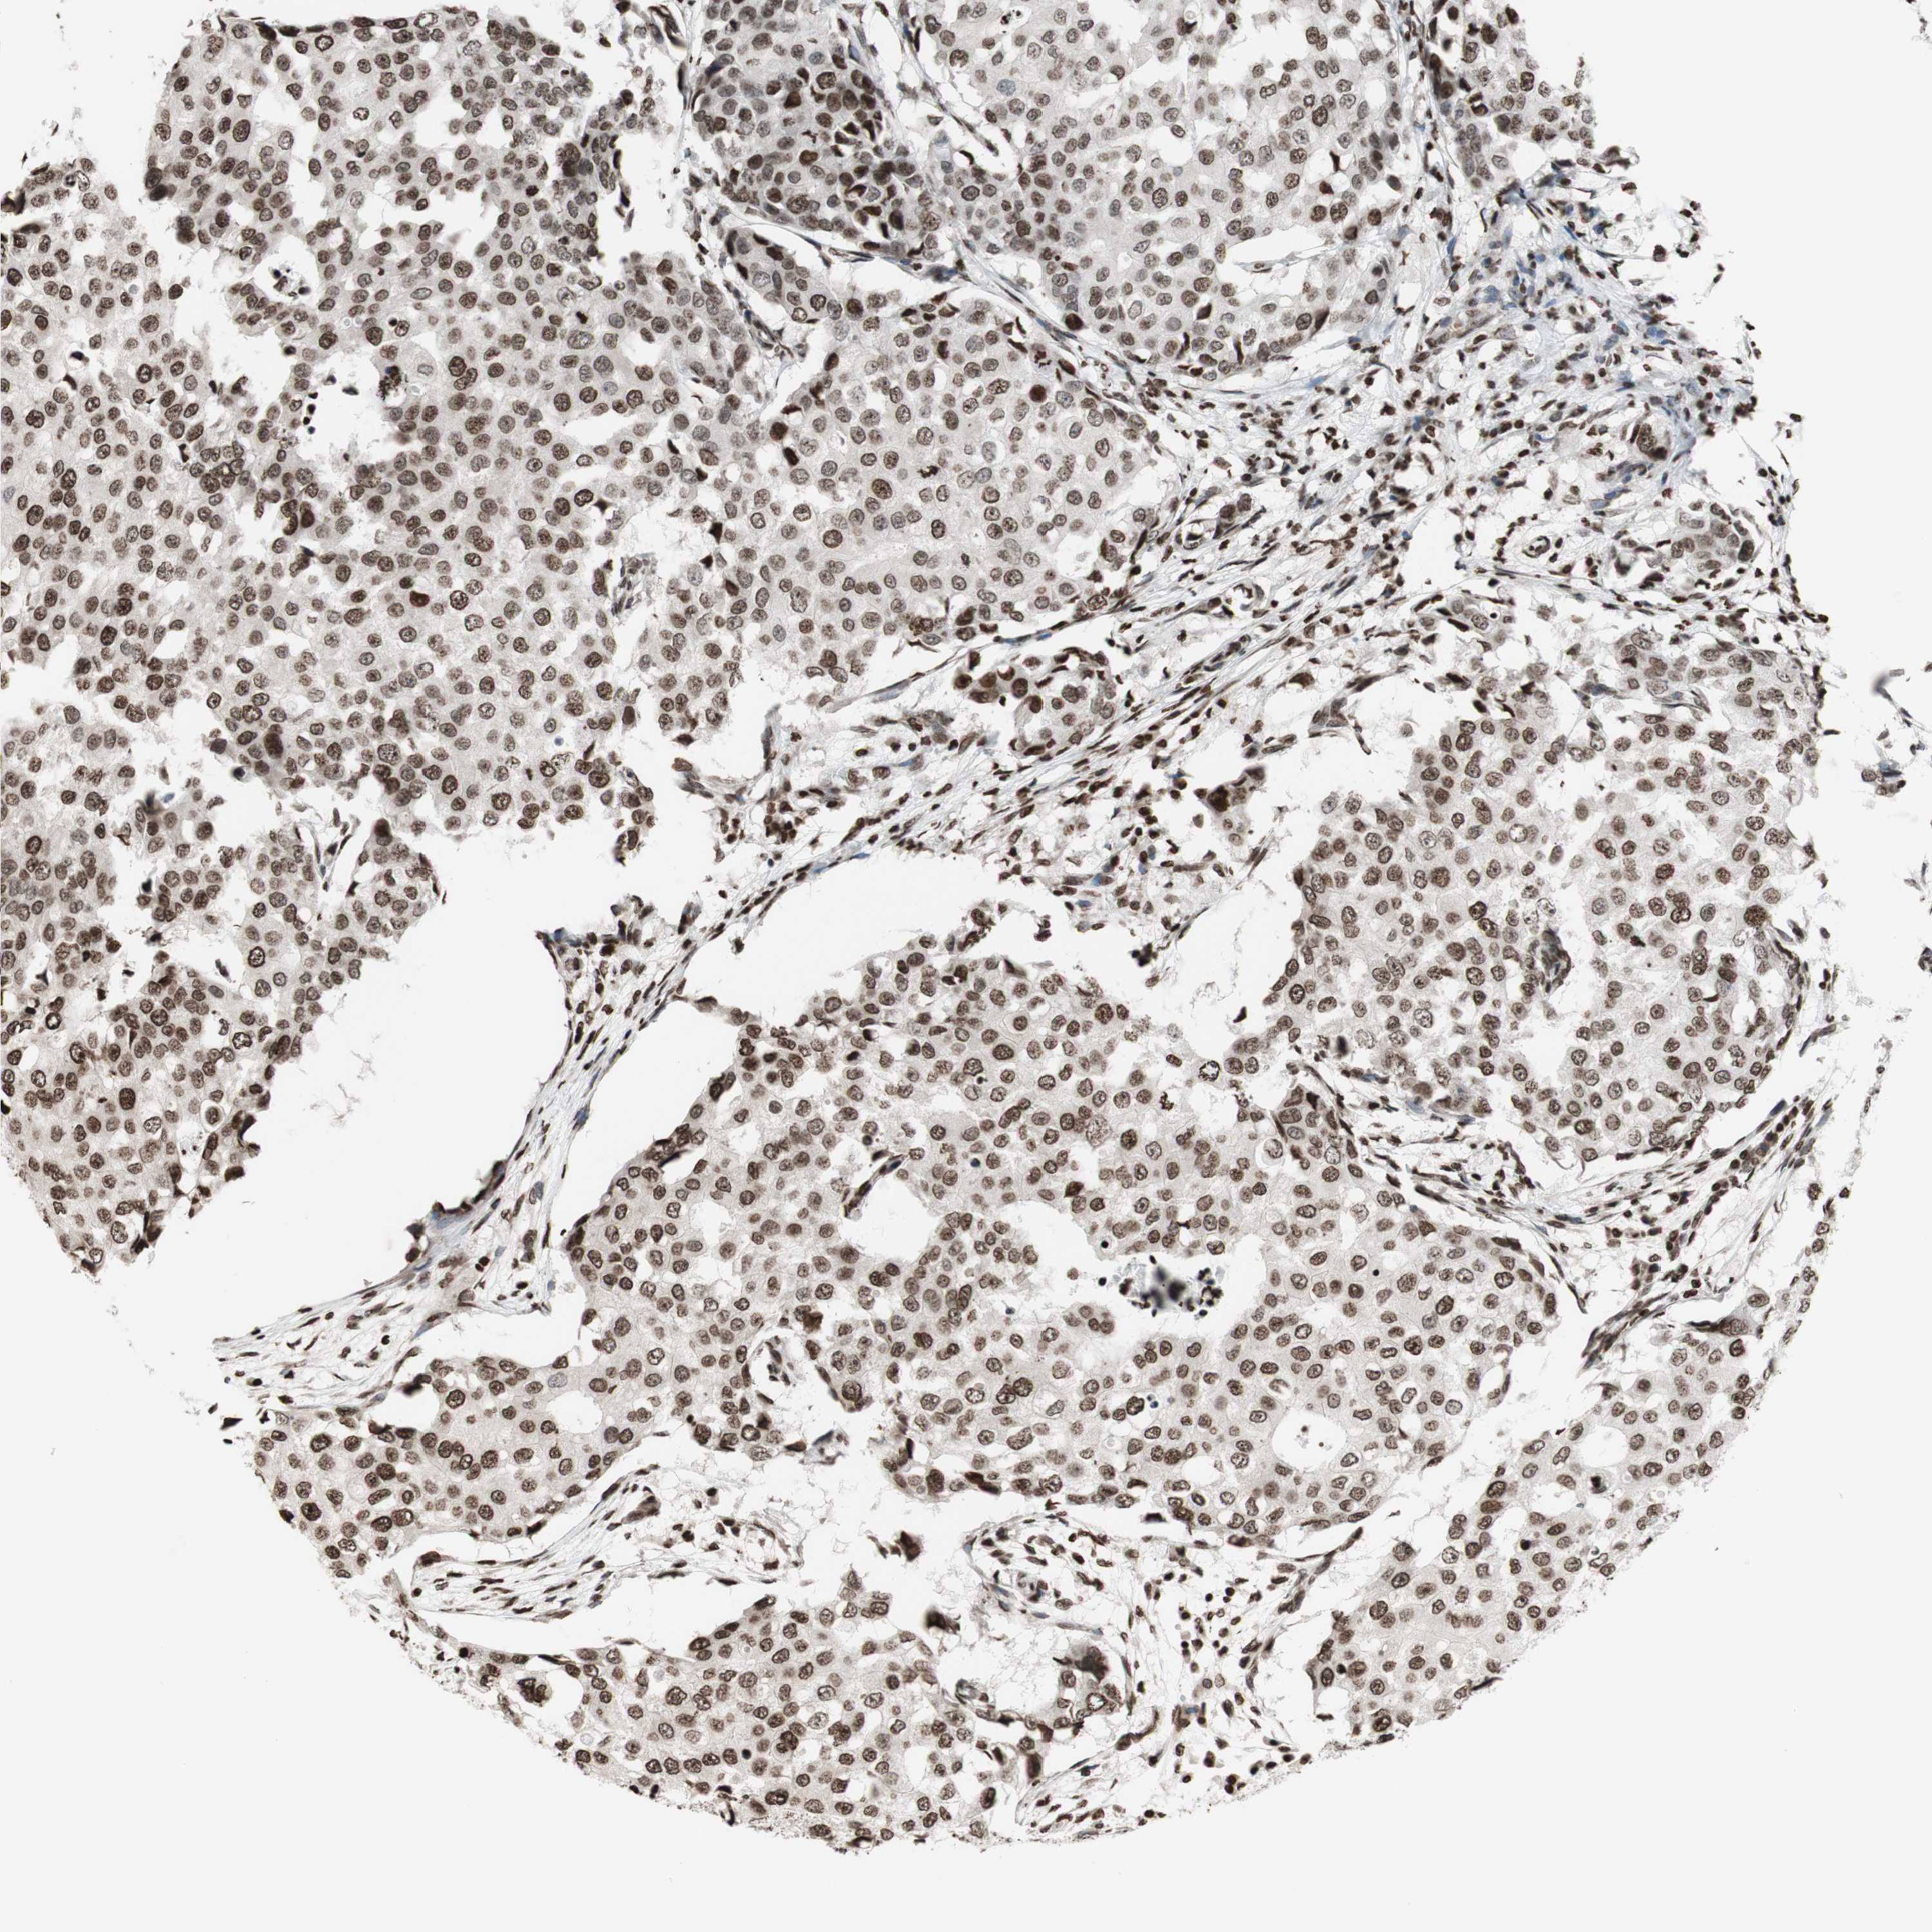

CANCER BREAST CANCER Show tissue menu

BRCA TCGA BRCA VALIDATION PROTEIN EXPRESSION